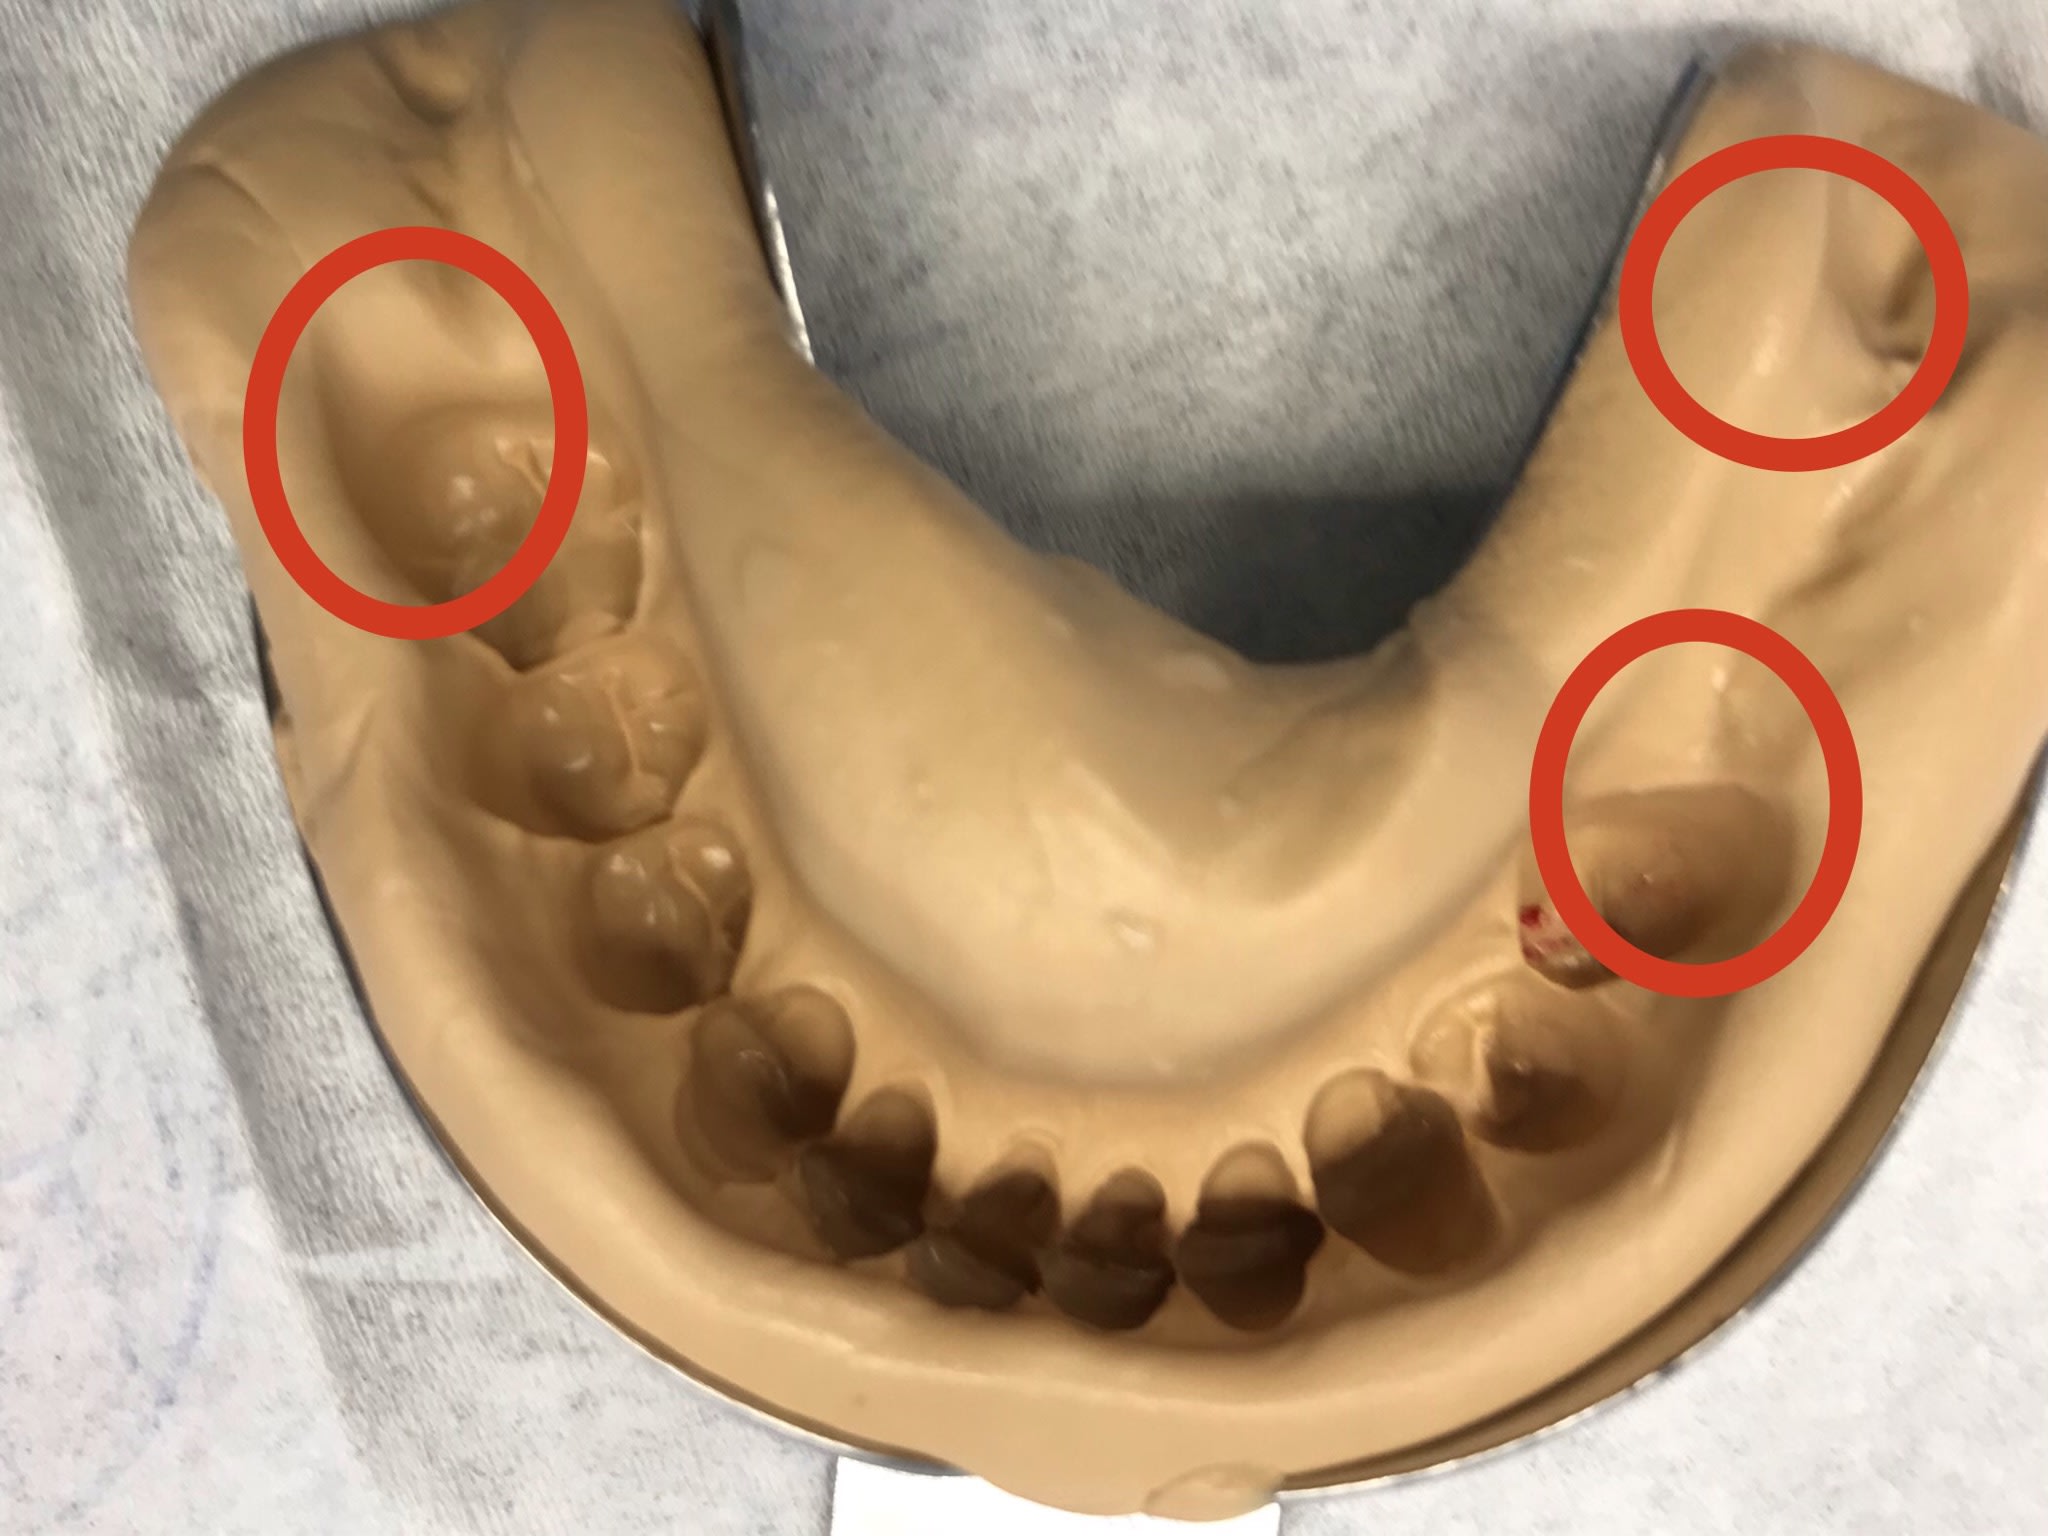

Il est toujours là gai-luron ? Voici la junior technique dont on avait parlé , c’est à dire la wash technique sans avoir besoin d’évider ton empreinte ou de mettre un film plastique ou autre .

1) du lourd. J’enlève mon PE, je remets mon PE en bouche, j’enlève je remets etc etc => les zones de manque correspondent au zones qui vont permettre de remettre le PE sans évider

2) du light

--

La forme de ma coupe de cheveux futuriste me permet une meilleure pénétration dans l'air et d' avoir moins de résistance face au vent lorsque je me déplace.

6f9c9f24 a8cd 43ff ae86 a410ca8b6a72 bqu5tx - Eugenol

Fac52c24 d661 40d6 8d84 e679f903cefd gi50bi - Eugenol